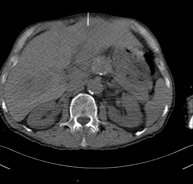

- TC Abdomen

Prueba diagnóstica que consiste en obtener imágenes del abdomen de alta definición anatómica (hígado, vesícula biliar, vía biliar, páncreas, bazo, estómago, intestinos, riñones, estructuras vasculares, vejiga, útero y ovarios, etc.) mediante el empleo de un equipo de TC (Tomografía Computarizada). Dichas imágenes se estudian posteriormente en una estación de trabajo que permite reconstrucciones bidimensionales en diferentes planos del espacio, y también reconstrucciones 3D (volumétricas). La mayoría de estudios requieren el empleo de contraste yodado para mejorar la definición de las imágenes. - TC Pelvis